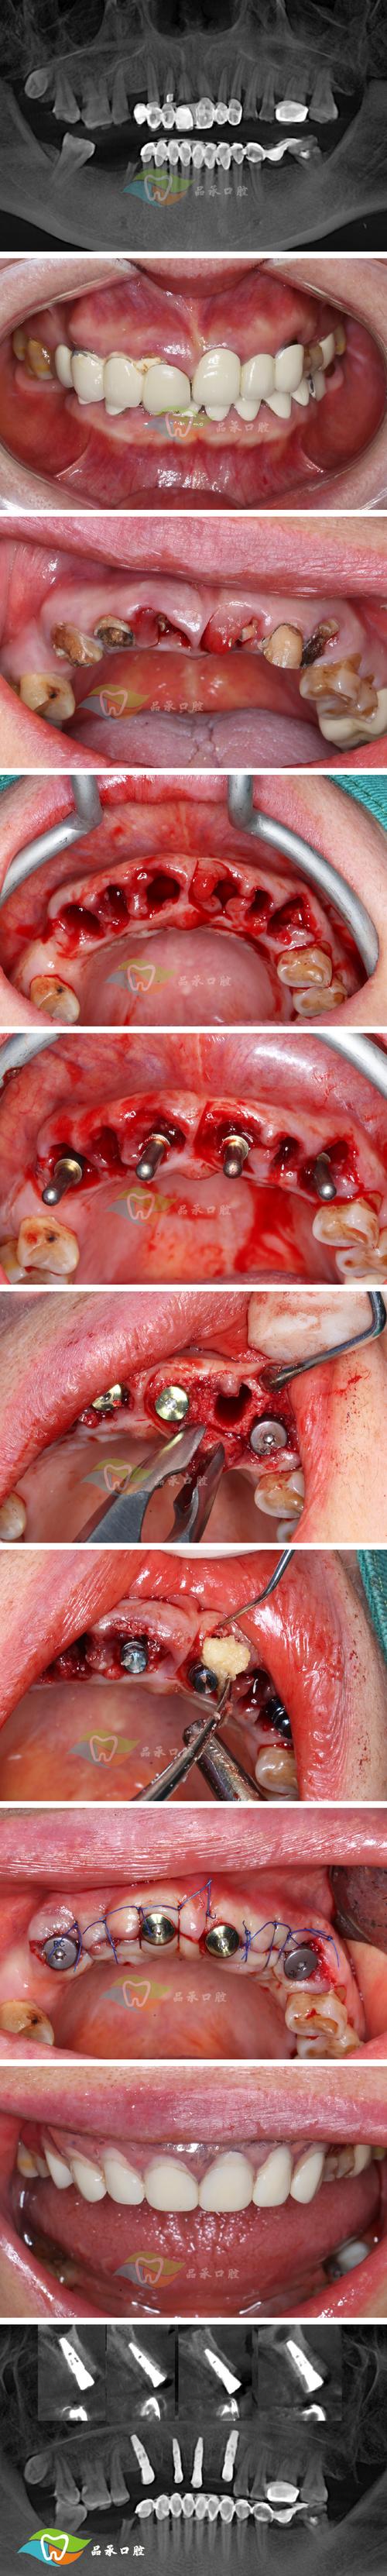

关于拔牙与神经的关系,需先了解口腔内的重要神经:下牙槽神经(支配下唇、颏部感觉)和上牙槽神经(支配上牙、上唇感觉),矫正中拔除的牙齿多为前磨牙(上下颌第一、第二前磨牙),这些牙的牙根位于牙槽骨内,距离下牙槽神经(位于下颌骨内)约1.5-2mm,且有骨壁相隔,正常拔牙操作不易损伤,而靠近神经的牙齿主要是下颌智齿(第三磨牙),其牙根可能贴近甚至包裹下牙槽神经,但矫正中拔智齿多因阻生、位置不正,而非常规拔牙,术前医生会通过全景片、CBCT(锥形束CT)精确测量牙根与神经的位置关系,设计拔牙路径,避免神经损伤。

拔牙后的处理与神经保护同样关键,拔牙后,医生会压迫止血、缝合伤口,减少出血和肿胀,术后24小时内避免刷牙漱口,防止血块脱落;48小时内冷敷面部减轻肿胀;饮食以温凉软食为主,避免用患侧咀嚼,若术后出现短暂麻木(如嘴唇、下巴),可能是局部麻醉或术后肿胀压迫神经,通常1-3周内恢复;若超过1个月仍麻木,需复查,可能是神经轻度损伤,通过营养神经药物(如维生素B1、甲钴胺)可促进恢复,严重神经损伤(如永久性麻木)概率低于0.5%,多与复杂牙根、解剖变异或操作不当有关。